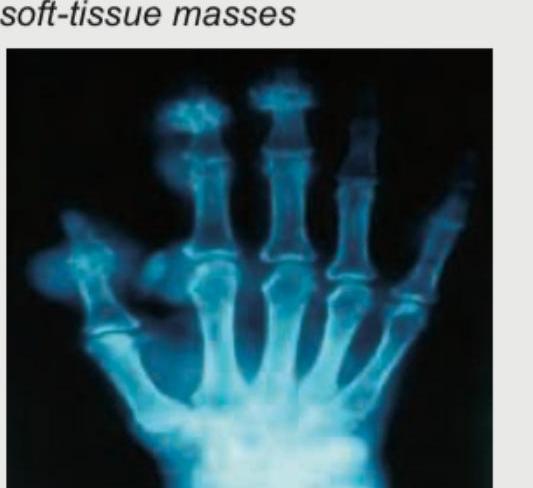

The clinical diagnosis favors development of chronic gout and the image shows presence of eccentric juxta-articular lobulated soft-tissue masses. Which of the following is the most definitive diagnostic test for gout shown in the image?

This elderly male came with a history of recurrent attacks of pain and swelling in the great toe in the past. This is the present X-ray of the hands. The diagnosis can be confirmed by:

Explanation: ***Polarized microscopy of tissue fluid aspirate*** - The definitive diagnosis of gout requires the identification of **monosodium urate crystals** in synovial fluid or tissue, typically performed with polarized microscopy. - This method directly visualizes the *negatively birefringent* (needle-shaped when perpendicular to the polarization axis) crystals, which are pathognomonic for gout. *X-ray of the joint* - X-rays can show characteristic changes in chronic gout, such as **punched-out erosions with overhanging edges** (known as Martel's sign) and soft tissue masses (tophi). - However, these findings are not specific to gout and can be seen in other conditions; they do not provide a definitive diagnosis on their own. *Blood tests for uric acid levels* - Elevated **serum uric acid levels (hyperuricemia)** are a key risk factor for gout, but they are neither necessary nor sufficient for diagnosis. - Many individuals with hyperuricemia never develop gout, and some patients can have normal uric acid levels during an acute gout attack. *MRI of the affected joint* - MRI can visualize soft tissue abnormalities like **tophi**, bone erosions, and inflammatory changes, offering detailed anatomical information. - While useful for assessing disease extent and complications, MRI cannot definitively identify the specific crystal deposits that confirm gout.

Explanation: ***Polarized microscopy of tissue fluid aspirate*** - The patient's history of recurrent pain and swelling in the **great toe**, along with the X-ray findings (which likely show features of crystal deposition such as **erosions with overhanging edges** or joint damage), is highly suggestive of **gout**. - **Gout** is definitively diagnosed by identifying **negatively birefringent needle-shaped urate crystals** within the synovial fluid or tissue aspirate under polarized microscopy. *HLA B27* - **HLA-B27** is a genetic marker associated with **spondyloarthropathies**, such as Caucasians with ankylosing spondylitis and psoriatic arthritis, not typically used for diagnosing gout. - While some spondyloarthropathies can affect the great toe, the clinical presentation and X-ray findings (which are presumably related to crystal deposition) are not characteristic of this condition. *Anti-CCP antibodies* - **Anti-CCP antibodies** (anti-cyclic citrullinated peptide antibodies) are a specific serological marker for **rheumatoid arthritis**. - Rheumatoid arthritis typically affects small joints symmetrically but does not primarily present with acute, recurrent painful swelling of the great toe or the characteristic X-ray changes seen in gout. *X-ray of lumbosacral spine* - An **X-ray of the lumbosacral spine** is indicated for conditions affecting the spine, such as ankylosing spondylitis or disc herniation. - While chronic gout can sometimes affect the spine, it is not the primary diagnostic tool for confirming gout, especially given the classic peripheral joint involvement.